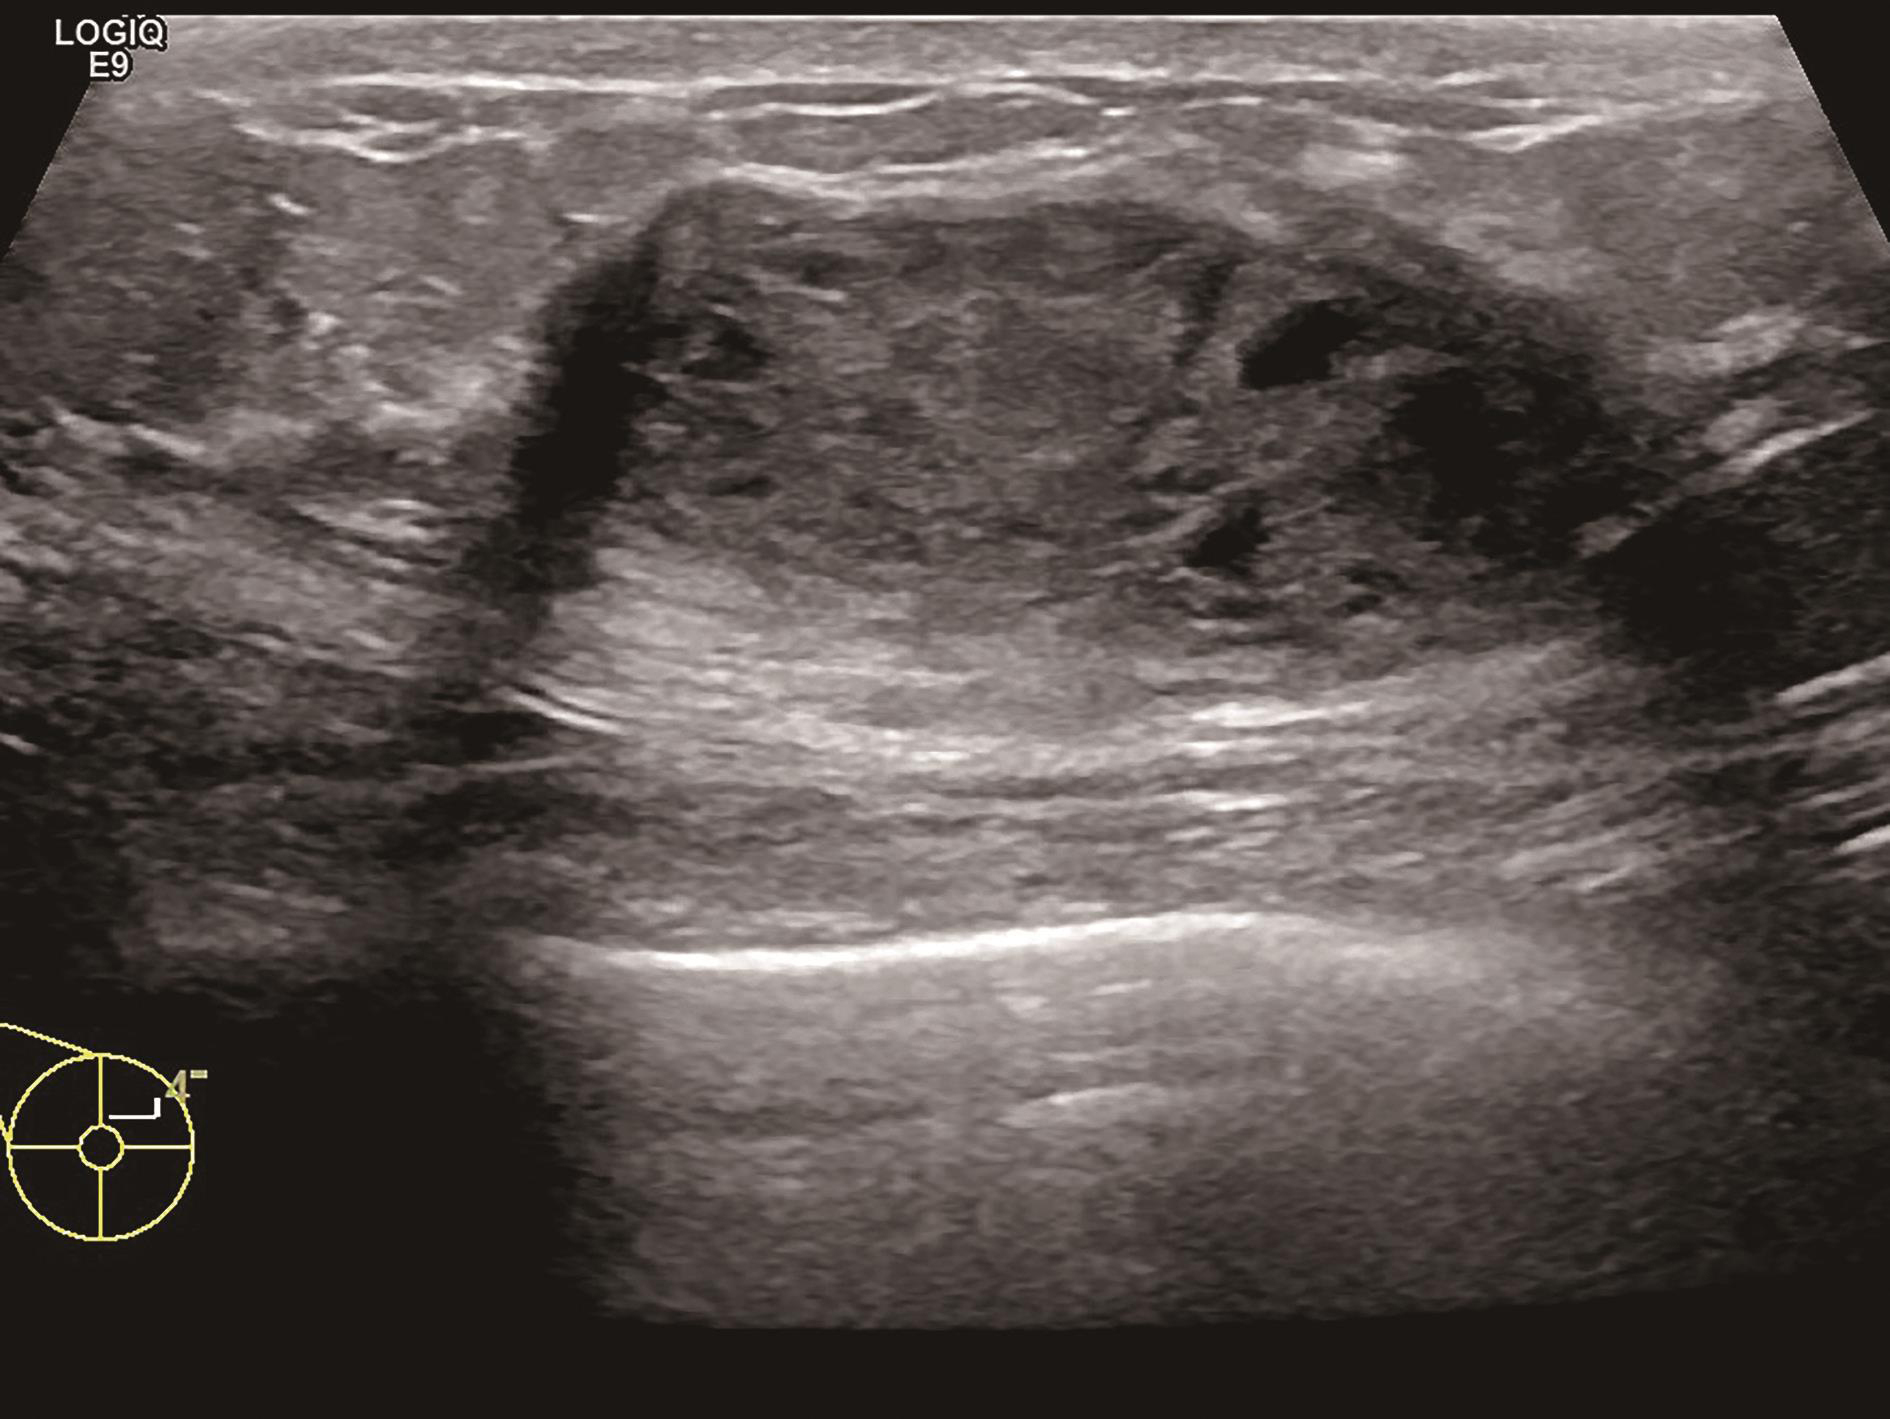

图2-2-3 病灶最大切面

图2-2-4 纵横比大于1或边界最不规整切面

图2-2-5 血流信号最丰富或有滋养血管切面